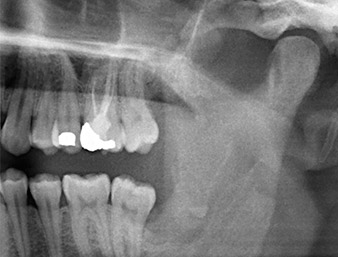

A 26-year old patient had recurring pain in the operative area six months after osteotomy of tooth 38 (LL8) and complained of hyposensitivity in the area innervated by the inferior alveolar nerve. He was referred by the referring dentist, who had not performed the original tooth extraction himself, to the Department of Oral Surgery at the University Dental Clinic Vienna.

The root remnant in the region of tooth 38 (LL8) was already displaying close proximity to the inferior alveolar nerve on the OPG. The root had fractured during the osteotomy but had not been removed by the primary treatment provider due to intraoperative pain. To ensure as little trauma as possible to the tissue, the new osteotomy was to be carried out using a piezo surgical system. The patient had an unremarkable medical history and was a non-smoker.

OPG 6 months after osteotomy

Fig. 1: OPG 6 months after osteotomy of tooth 38 (LL8): radix relicta lies close to the inferior alveolar nerve.

Based on his medical history, our patient (non-smoker, 26 years old) had a very good chance of a successful outcome. Due to indication of the root remnant’s close proximity to the inferior alveolar nerve on the OPG, digital volume tomography was used in addition (6).